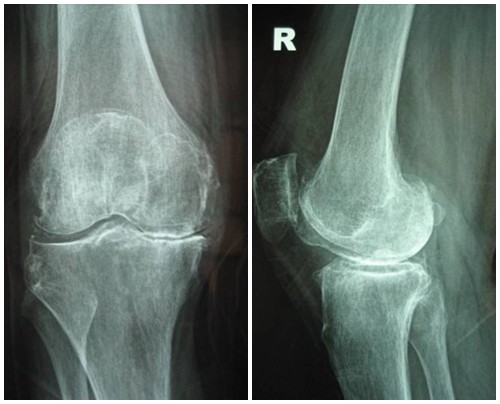

4. Giai đoạn 4: Thoái hóa khớp gối độ 4

Hình ảnh của khớp gối trên phim X-quang: Khe khớp hẹp nhiều, gai xương có kích thước lớn, đặc xương dưới sụn, đầu xương biến dạng rõ.

Thoái hóa khớp gối giai đoạn 4 là giai đoạn nặng, sụn khớp bị bào mòn

Thoái hóa khớp gối đã bước vào giai đoạn nặng, sụn khớp bị bào mòn và bong tróc gần như hoàn toàn để lộ đầu xương rõ rệt. Khoảng không gian chung giữa hai đầu xương thu hẹp đáng kể, gai xương ngày càng lớn, chất nhờn bôi trơn khớp giảm nên gây ra hiện tượng ma sát giữa hai đầu xương, gây đau nhức xương khớp nghiêm trọng. Người bệnh xuất hiện một loạt các triệu chứng đau nhức liên tục, cứng khớp, khó vận động khớp, khó đi lại… ảnh hưởng đến sinh hoạt. Theo thời gian, thoái hóa khớp gối có thể gây biến dạng khớp hoàn toàn, gây lệch trục khớp…